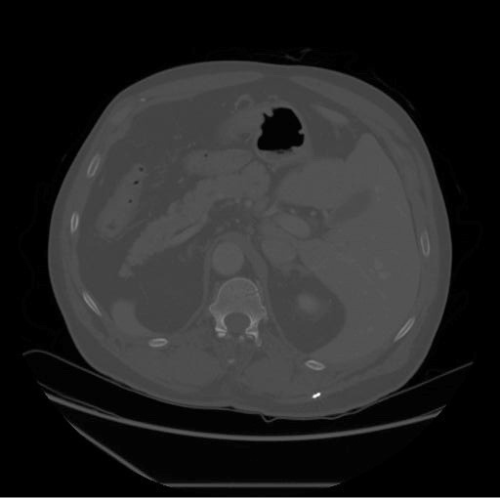

As shown in Fig. 2, we ensure that contrast enhancement is applied dynamically and adapts to each individual image by leveraging the underlying grayscale intensity distribution, rather than imposing uniform adjustments across the entire dataset. The enhanced output is subsequently validated and converted to an 8-bit representation to ensure numerical stability and compatibility with downstream processing. The pipeline supports parallel batch processing with consistent configuration settings, while allowing key parameters, such as the background intensity threshold, percentile bounds for contrast stretching, CLAHE clip limit [48], and tile grid size, to be tuned for specific datasets. Artifact suppression is achieved through smooth histogram redistribution, bilinear interpolation between tiles, and edge-aware processing strategies. This preprocessing design is particularly well suited for low-contrast medical images, especially CT and MRI scans, where preserving subtle anatomical details is essential for reliable diagnosis and accurate segmentation in subsequent deep learning pipelines.

For experimental evaluation, we leveraged three publicly available medical imaging datasets. The FLARE22 dataset [33] served as the primary source for training and validation, while additional samples from the SAROS [40] and CHAOS [25] datasets were incorporated for extended testing and validation. All datasets comprise abdominal CT and MRI scans provided in NIfTI format; however, instead of processing full 3D volumes, we extracted 2D axial slices for analysis. Middle axial slices were selected, as they consistently offer clear visualization of key abdominal organs and representative anatomical context. While FLARE22 forms the core experimental dataset, the inclusion of SAROS and CHAOS enables assessment of the robustness and generalizability of the proposed approach across varying imaging protocols and scanner characteristics.